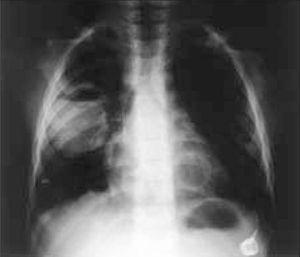

Niño de 3 años que presenta de forma aguda fiebre alta y tos productiva. Afecto de hemofilia A2 es portador de un port-a-cath (PAC) para la administración del factor VIII recombinante. A la exploración física destaca hipofonesis en la base pulmonar derecha con estado general conservado y sin signos de dificultad respiratoria. La zona del PAC no muestra signos inflamatorios y el resto de la exploración es normal. Se realiza una radiografía de tórax en la que se aprecian múltiples imágenes cavitarias, algunas de ellas con nivel hidroaéreo (fig. 1). En la analítica sanguínea destacan 20.650 leucocitos/μl (72 % neutrófilos; 26 % linfocitos; 2 % monocitos) y proteína C reactiva de 334 mg/l. Se recogen hemocultivos a través del PAC y transcutáneo. La TC informa de la presencia de varias cavidades de pared gruesa con nivel hidroaéreo en la mayoría, diseminadas en ambos campos pulmonares, destacando una de 5 cm en lóbulo inferior derecho y otra con contenido aéreo, de 2 cm de diámetro, en lóbulo inferior izquierdo (figs. 2A y B). Ingresa con la orientación diagnóstica de abscesos pulmonares múltiples iniciándose tratamiento empírico intravenoso con cefotaxima, vancomicina y metronidazol. Al tercer día de ingreso se confirma la presencia de Staphylococcus aureus sensible a cloxacilina en ambos hemocultivos, por lo que se continúa con dicho antibiótico en monoterapia. Se procede a retirar el PAC y al drenaje percutáneo guiado por escopia del absceso de mayor tamaño, confirmándose en el cultivo del pus la presencia de S. aureus. El tratamiento intravenoso se mantiene 3 semanas y se continúa por vía oral durante 15 días. La evolución es favorable y el control radiológico a las 3 semanas muestra cavidades aéreas residuales.

Figura 1. Radiografía de tórax: se observan imágenes cavitarias, la de mayor tamaño situada en el lóbulo inferior derecho.